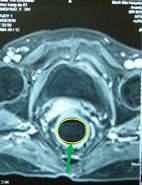

Sau điều trị hóa-xạ trị 33 ngày khối u trực tràng đã tan hết